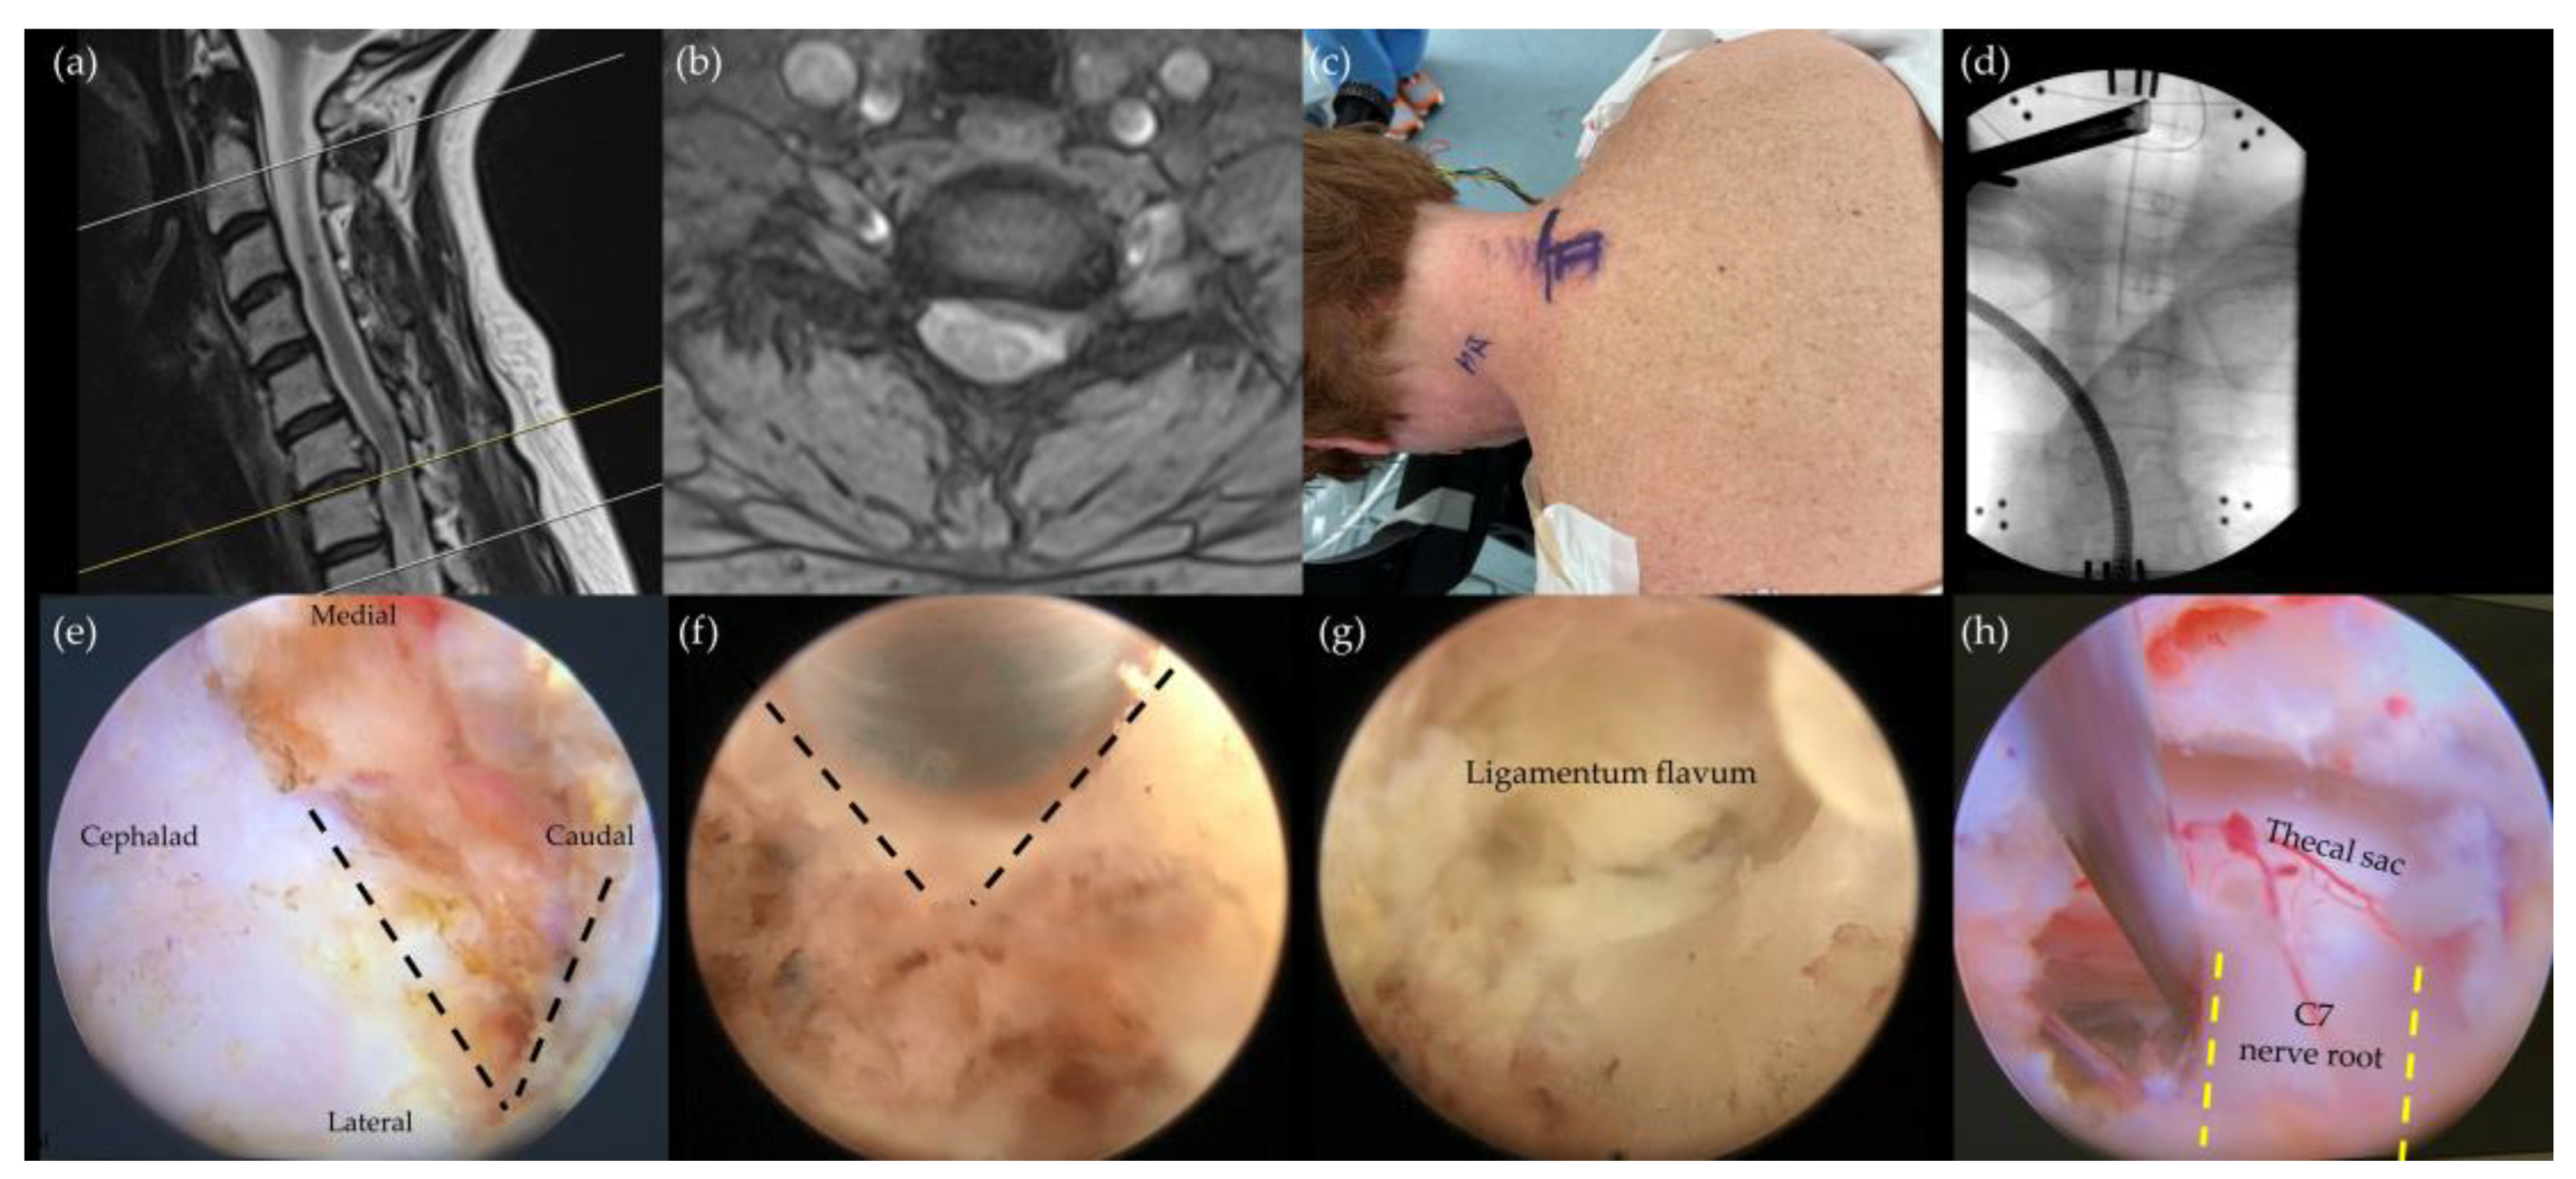

4.1. Posterior Endoscopic Cervical Foraminotomy/Discectomy (PECF/PECD)